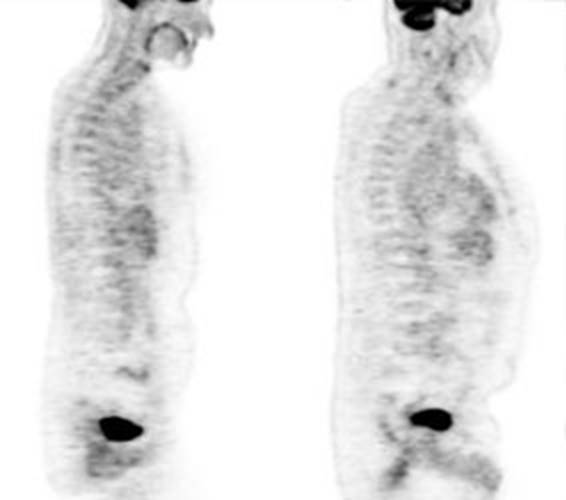

Figure 21 - Marrow activity: The images below are from

two separate patients each showing mild FDG accumulation within the vertebral

bodies.

Figure 22 - Growth colony effect: The patient shown below

had received growth colony stimulating factor (GCSF). Note the extensive

increased marrow activity. Note increased splenic activity also seen as a result of GCSF therapy.